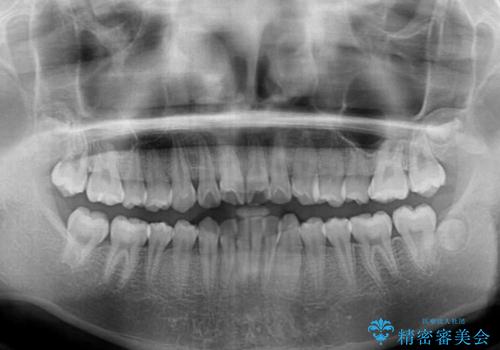

- 上下前歯のデコボコを改善したいとのことで来院された患者様です。

中学生と言うこともあり、1年強の短期間で終了しました。

歯磨きがしっかりとできないと虫歯になるリスクがありましたが、治療期間中は清潔な状態を保っていただけました。